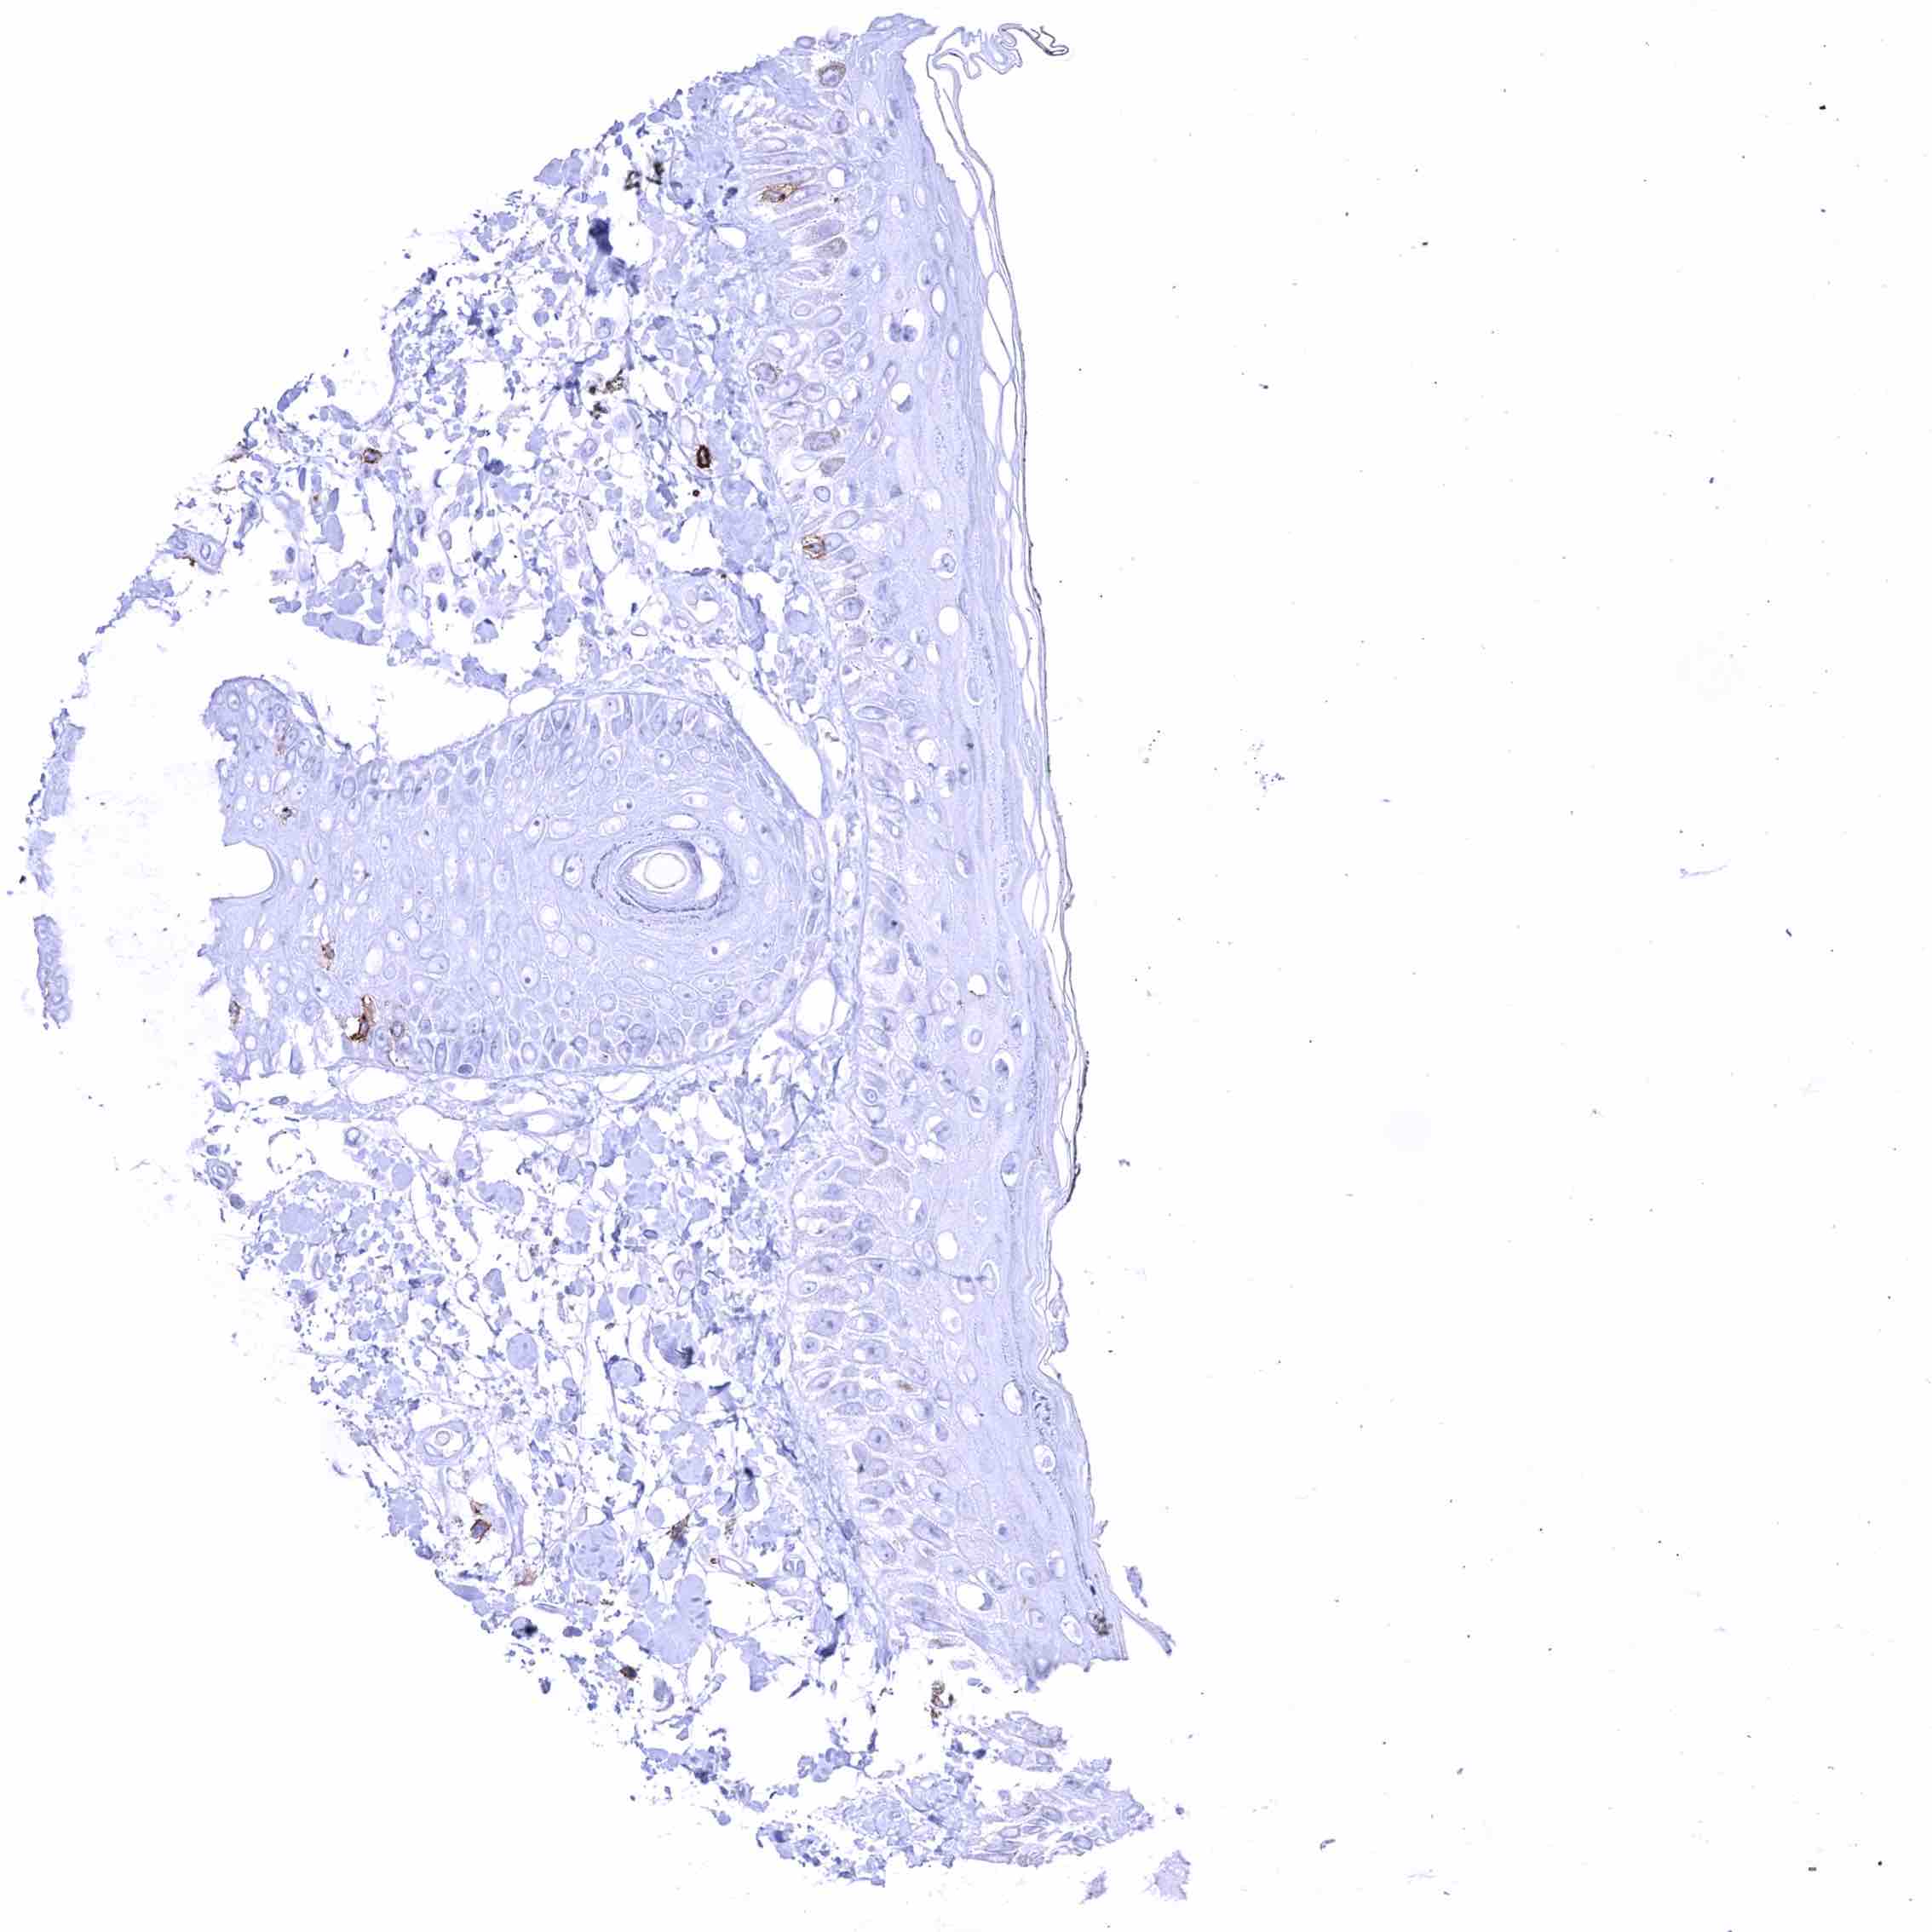

Skin – Membranous CD70 staining of few intraepithelial cells (probably lymphocytes).

Skin, hairfollicel and sebaceous glands